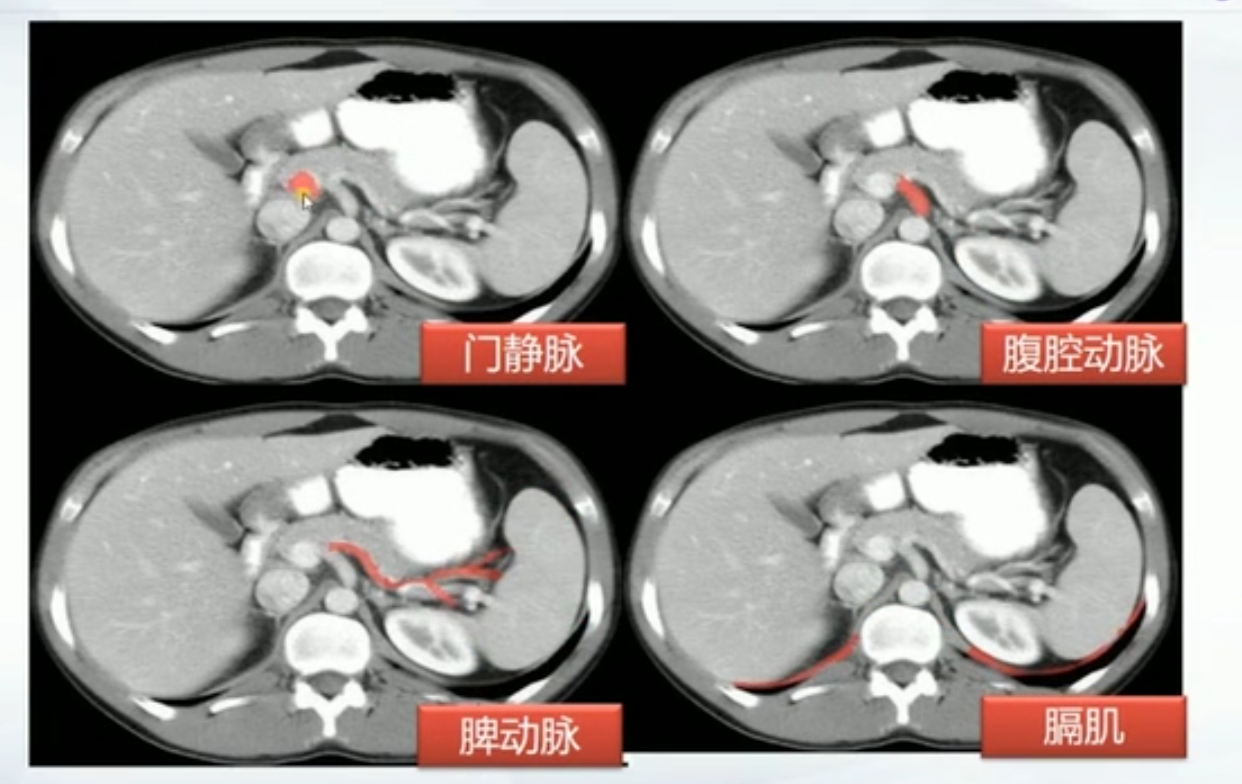

肝CT

- 40~60HU,高于胰,脾

- 肝内管道系统(胆管,肝动脉静脉和门静脉)低于实质,周围小分支多不显示。大血管呈低密度树状影

正常肝重要结构